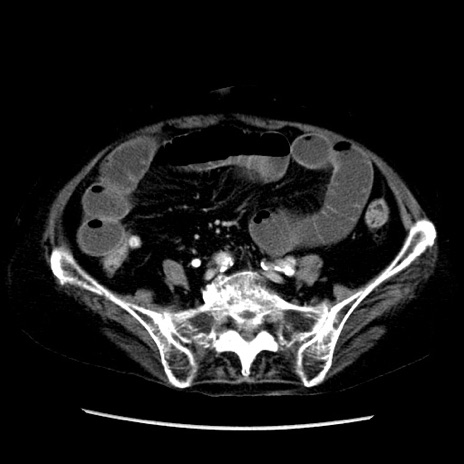

症例

冠状断像